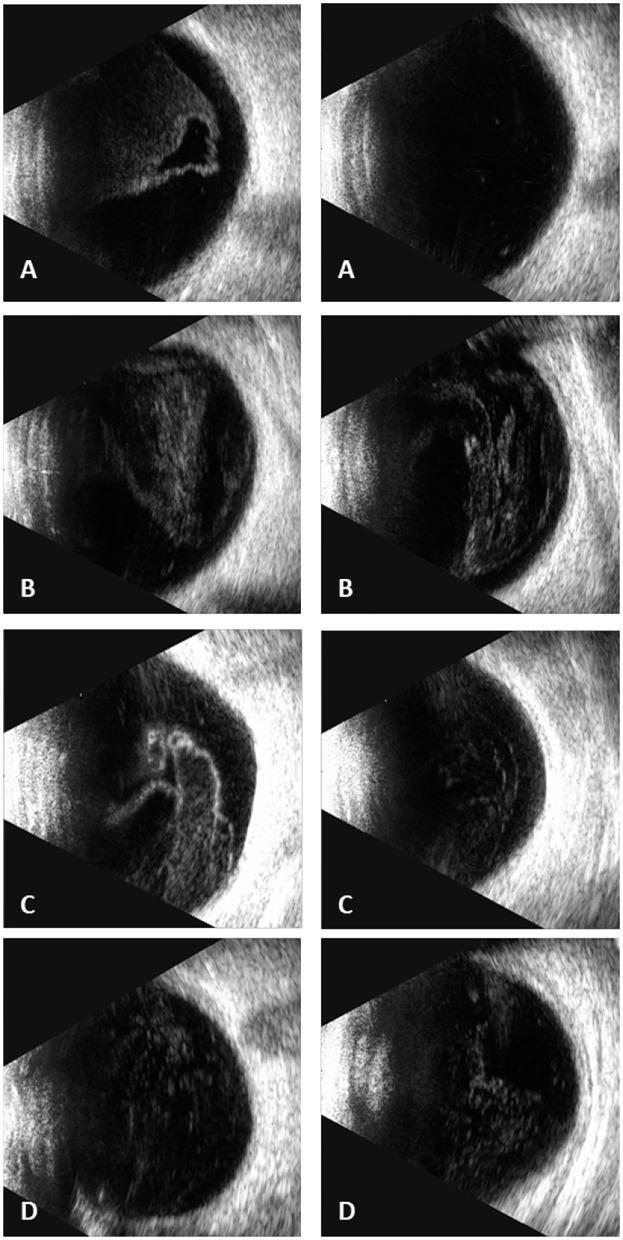

With HAART, plasma levels of CD4 T cell counts rose remarkably. The mean baseline CD4 count of the four patients was 14.5 (range from 7 to 33) cells/μl before HAART and 183.25 (range from 153 to 220) cells/μl when diagnosed with CMV-IRR. Ophthalmic examination demonstrated severe vitreous opacities and necrotizing retinitis, intraretinal hemorrhages, and vasculitis. A large number of CMV sequencing was detected by DNA sequencing of vitreous samples. All four patients were recovered from CMV-IRR with anti-CMV and corticosteroid treatment.

随着HAART治疗,血浆CD4 T细胞计数显著上升。这4例患者HAART治疗前的平均基线CD4计数为14.5(范围为7至33)个细胞/微升,诊断为CMV-IRR时为183.25(范围为153至220)个细胞/微升。眼科检查显示严重的玻璃体混浊、坏死性视网膜炎、视网膜内出血和血管炎。通过玻璃体样本的DNA测序检测到大量CMV序列。所有4例患者经抗CMV和皮质类固醇治疗后均从CMV-IRR中康复。